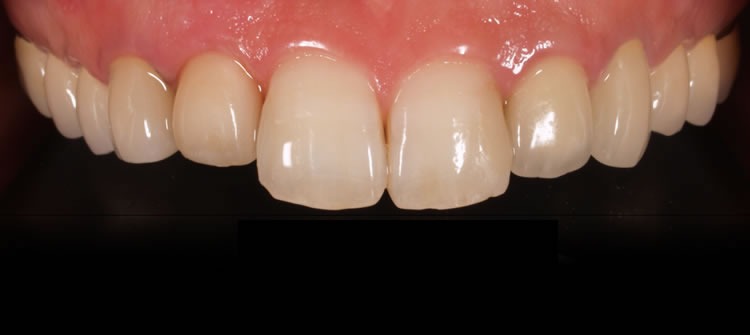

ファイナルレストレーション